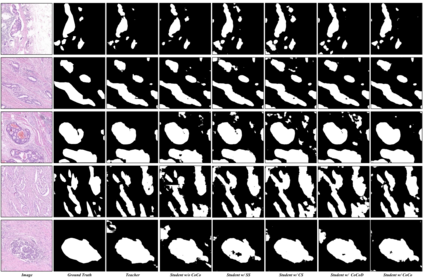

In recent years, deep convolutional neural networks have made significant advances in pathology image segmentation. However, pathology image segmentation encounters with a dilemma in which the higher-performance networks generally require more computational resources and storage. This phenomenon limits the employment of high-accuracy networks in real scenes due to the inherent high-resolution of pathological images. To tackle this problem, we propose CoCo DistillNet, a novel Cross-layer Correlation (CoCo) knowledge distillation network for pathological gastric cancer segmentation. Knowledge distillation, a general technique which aims at improving the performance of a compact network through knowledge transfer from a cumbersome network. Concretely, our CoCo DistillNet models the correlations of channel-mixed spatial similarity between different layers and then transfers this knowledge from a pre-trained cumbersome teacher network to a non-trained compact student network. In addition, we also utilize the adversarial learning strategy to further prompt the distilling procedure which is called Adversarial Distillation (AD). Furthermore, to stabilize our training procedure, we make the use of the unsupervised Paraphraser Module (PM) to boost the knowledge paraphrase in the teacher network. As a result, extensive experiments conducted on the Gastric Cancer Segmentation Dataset demonstrate the prominent ability of CoCo DistillNet which achieves state-of-the-art performance.